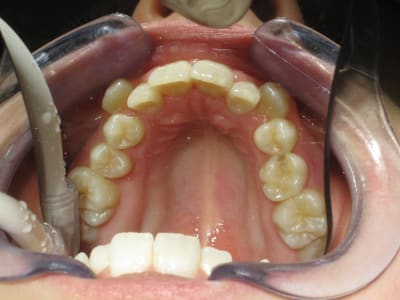

Je precise que je ne suis vraiment pas une fleche en ortho et que je veux bien apprendre certaines choses. Ma question donc ; lorsque vous voyez une patiente revenir comme sur les photos suivantes après traitement par expander ; c'est normal pour vous ? C'est le resultat que l'on est en droit d'attendre après 2500 dollars d'expansion ? Ou alors est-ce, comme je commence a le renifler, le resultat suffisant pour avoir elargi un petit peu tout en restant absolument certain de se garder au chaud pour dans quelques semestres, un inevitable traitement complet par 'braces' ou Invisalign (2 ans, 8500 a 11.500 AUD).

Bref, j'aimerai bien avoir l'avis de specialsites concernant au moins le cas presente ; les photos sont prises après le port d'un expander (et de memoire avant c'etait pas bien pire). La patiente a 11 ans.

Oui, j'ai vu la carie en mesial de 55 ;-)